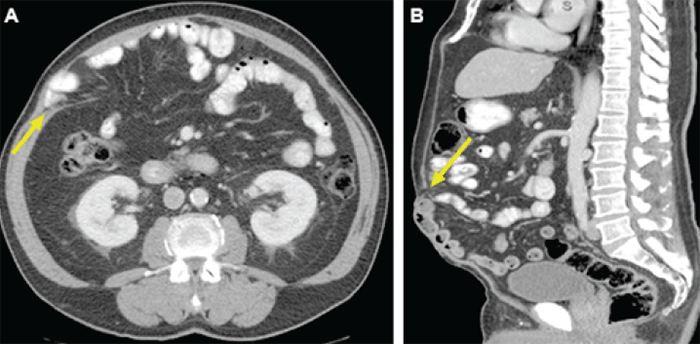

In the second case, the patient, a 44-year-old man, presented with a history of renal cell carcinoma for which he underwent an open right nephrectomy. His operation was complicated by a small bowel perforation which required emergent right hemicolectomy with ileocolic anastomosis. He subsequently developed a large, symptomatic incisional hernia. Preoperative CT scan showed significant loss of intra-abdominal domain with >7.5 cm diastasis between the rectus and internal oblique muscles (Figure 2).

Figure 2. Preoperative CT Scans: Right-sided Incisional Hernia Lateral to Rectus Abdominis Muscle. Published with Permission